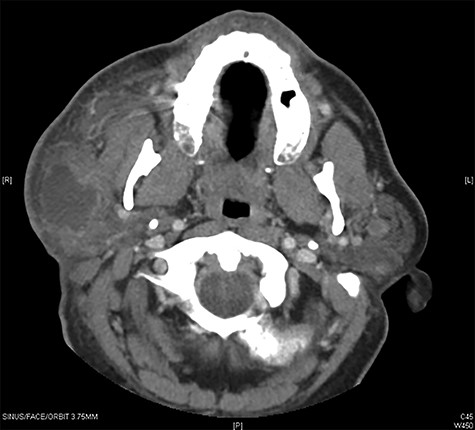

Computed tomography (CT) with contrast (Fig. 1) showed a right parotid gland fluid collection identified within the superficial lobe of the parotid gland with enlarged lymph nodes present in various levels of the neck. Fine-needle aspiration (FNA) revealed a cyst of the right parotid gland. A right superficial parotidectomy with nerve monitoring was performed and a well-circumscribed mass was excised. Pathology revealed a BLEC of the right superficial parotid measuring 3.5 × 2.5 × 2.1 cm.

Maxillofacial Axial CT with contrast in the area of clinical interest demonstrating a 4 × 4.4 × 2 cm (AP, vertical transverse) well-circumscribed lesion in the right parotid superficial gland.